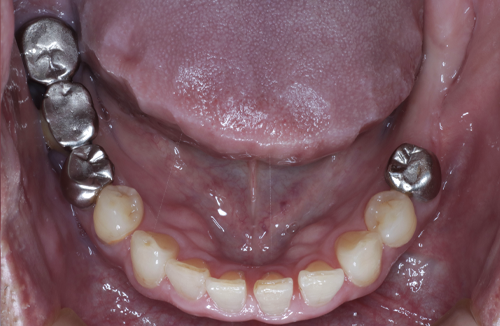

【お悩み】

奥歯を失ったまま過ごしていましたが、「手術が怖い」「本当に大丈夫なのか不安」という気持ちから治療に踏み切れずにいました。

【診断】

CT検査を行い、インプラント治療が可能な骨の状態であることを確認しました。

【治療内容】

治療前にしっかりと説明を行い、患者さまにご納得いただいたうえでインプラント治療を進めました。

【治療後】

治療後は違和感も少なく、「もっと早く相談すればよかった」とお話しされています。

【この症例のポイント】

不安を感じている方こそ、まずは状態を正確に知ることが大切です。

治療を受けるかどうかは、相談後に決めていただけます。